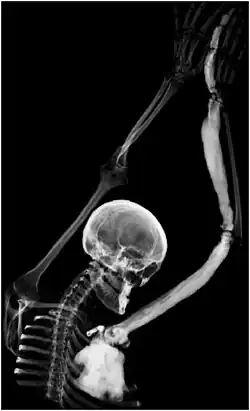

Мелореостоз (болезнь Лери, ризомономелореостоз) — доброкачественная дисплазия,[2] врождённая патология костной ткани, проявляющаяся её резким уплотнением (остеосклерозом). Мелореостоз затрагивает в той или иной степени кости одной из верхних или нижних конечностей; в редких случаях поражается позвоночник или нижняя челюсть.[3]

Клинические проявления мелореостоза могут быть неспецифичны и ограничиваться монотонными, тупыми скелетно-мышечными болями в поражённой конечности; в некоторых случаях имеют место сильные боли, деформация костей с функциональными ограничениями и контрактурами; трофические нарушения. Патогномоничным симптомом мелореостоза при рентгенографии является картина «стекающего со свечи воска» в виде продольных сплошных или прерывистых полос уплотнения костной ткани. В соседних отделах костная ткань не изменена или несколько порозна.